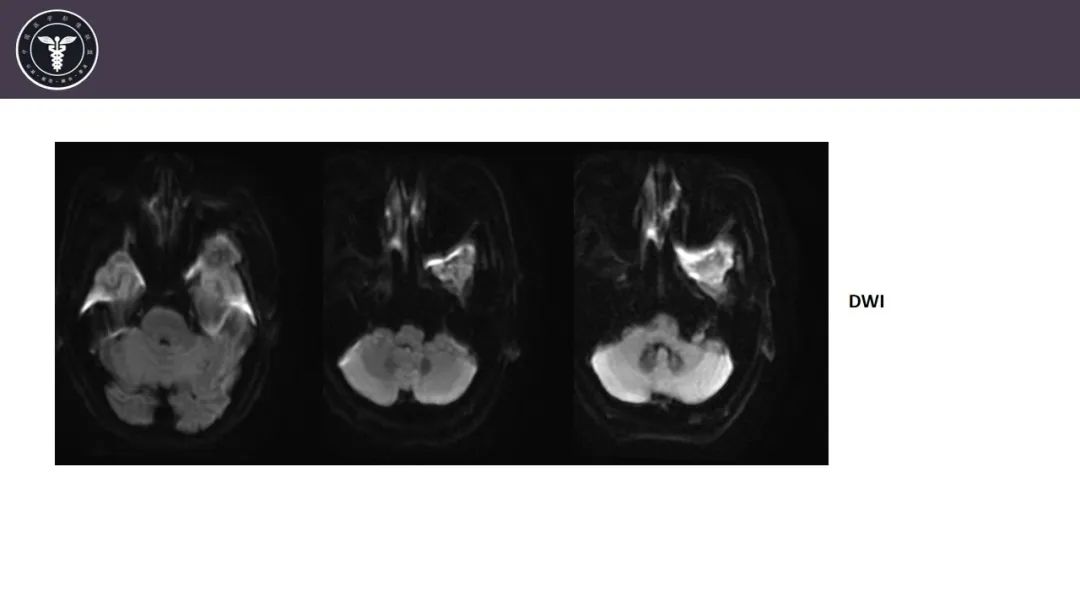

【病例】咬肌间隙肌纤维母细胞肉瘤1例MR诊断与鉴别-3